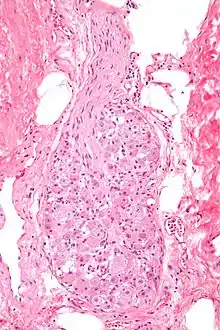

![]() صورة مجهرية للعُقدة مَصبوغة بواسطة صبغة الهيماتوكسيلين والأيوزين | |